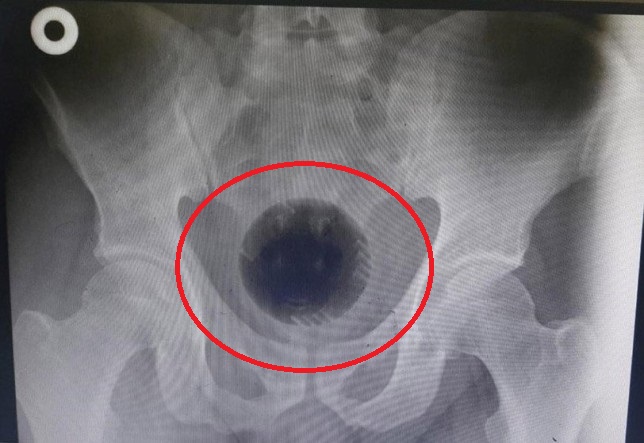

Ảnh chụp X-quang cho thấy quả bóng trong trực tràng của người đàn ông

Một người đàn ông, 51 tuổi ở Anh phải đến bệnh viện cấp cứu vì cảm thấy quá đau bụng. Sau khi thăm khám, bác sĩ xác định 1 vật như quả bóng, là bộ phận trong máy giặt thảm đã mắc kẹt trong trực tràng bệnh nhân. Dị vật hình tròn có đường kính khoảng 7-8 cm.